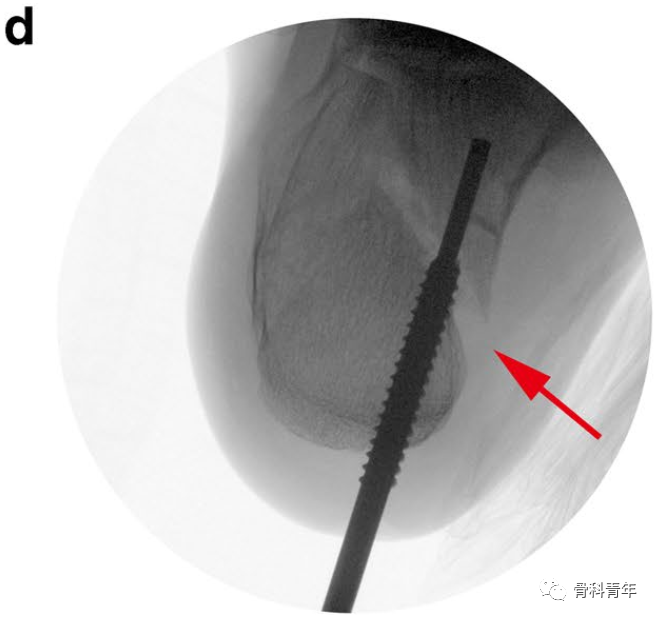

3.经克氏针,置入外套筒,将外套螺钉置入跟骨后结节骨块,螺纹不穿出骨折线;此时拔除克氏针,经外套T柄内外翻及牵引,可初步恢复内翻及高度,及松解骨块间的卡压。

4.拔除克氏针后,经外套筒置入内套,内套实心杆穿过骨折线,置入载距突骨块,并不穿出。此时内套近端螺纹与外套筒内侧螺钉咬合,转动内套T型柄,可实现内外套间的相向运动,由于外套空心螺钉固定于后结节骨块,此运动即可实现对载距突骨块撑起作用。

5.复位见关节面塌陷恢复后,克氏针临时固定,可进行后续固定操作。